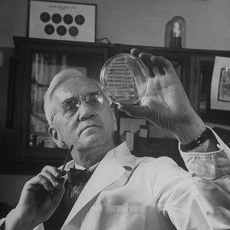

11. PENICILINA

Alexander Fleming era um médico bastante desorganizado e que mantinha sempre o seu ambiente de trabalho num caos. No entanto, esse mau hábito acabaria por dar origem a uma descoberta que revolucionou a medicina. Em 1928, no hospital Saint Mary’s, em Londres, o médico observava uma colônia de Staphylococcus aureus. Numa manhã, ao chegar ao laboratório, ele percebeu que tinha deixado a porta aberta e por isso um dos seus cultivos de micróbios apresentava uma cor esverdeada. Ele concluiu logo que o fungo teria, provavelmente, sido proveniente do andar de baixo, onde estava curiosamente o laboratório dos fungos. Em vez de ter uma atitude negativa, ele resolveu tentar perceber o que tinha acontecido. Ele concluiu que o fungo Penicilium tinha morto todas as bactérias. A partir dele, extraiu a penicilina.

Alexander Fleming era um médico bastante desorganizado e que mantinha sempre o seu ambiente de trabalho num caos. No entanto, esse mau hábito acabaria por dar origem a uma descoberta que revolucionou a medicina. Em 1928, no hospital Saint Mary’s, em Londres, o médico observava uma colônia de Staphylococcus aureus. Numa manhã, ao chegar ao laboratório, ele percebeu que tinha deixado a porta aberta e por isso um dos seus cultivos de micróbios apresentava uma cor esverdeada. Ele concluiu logo que o fungo teria, provavelmente, sido proveniente do andar de baixo, onde estava curiosamente o laboratório dos fungos. Em vez de ter uma atitude negativa, ele resolveu tentar perceber o que tinha acontecido. Ele concluiu que o fungo Penicilium tinha morto todas as bactérias. A partir dele, extraiu a penicilina.

Mas o que tem de tão revolucionário nesta pesquisa? Na verdade, a penicilina é um bactericida que não é tóxica para o ser humano, pode ser usada para combater infecções sem enfraquecer as defesas do organismo. No final, Fleming explicou que “não foi ele que inventou a penicilina”, mas sim a natureza. Mas esta não tinha sido a primeira vez que este cientista tinha beneficiado da sua desorganização. Já em 1922, ele estava estudando a proliferação de micróbios em colônias cultivadas a partir de secreções nasais e, sem querer, por estar resfriado, deixou cair uma lágrima sobre a placa. Um dia depois, ele verificou que o local onde a sua lágrima tinha caído não continha qualquer micróbio. Com isso ele concluiu que o corpo humano contém tecidos e secreções que possuem uma substância, a lisoenzima, que tem a capacidade de dissolver certas bactérias.